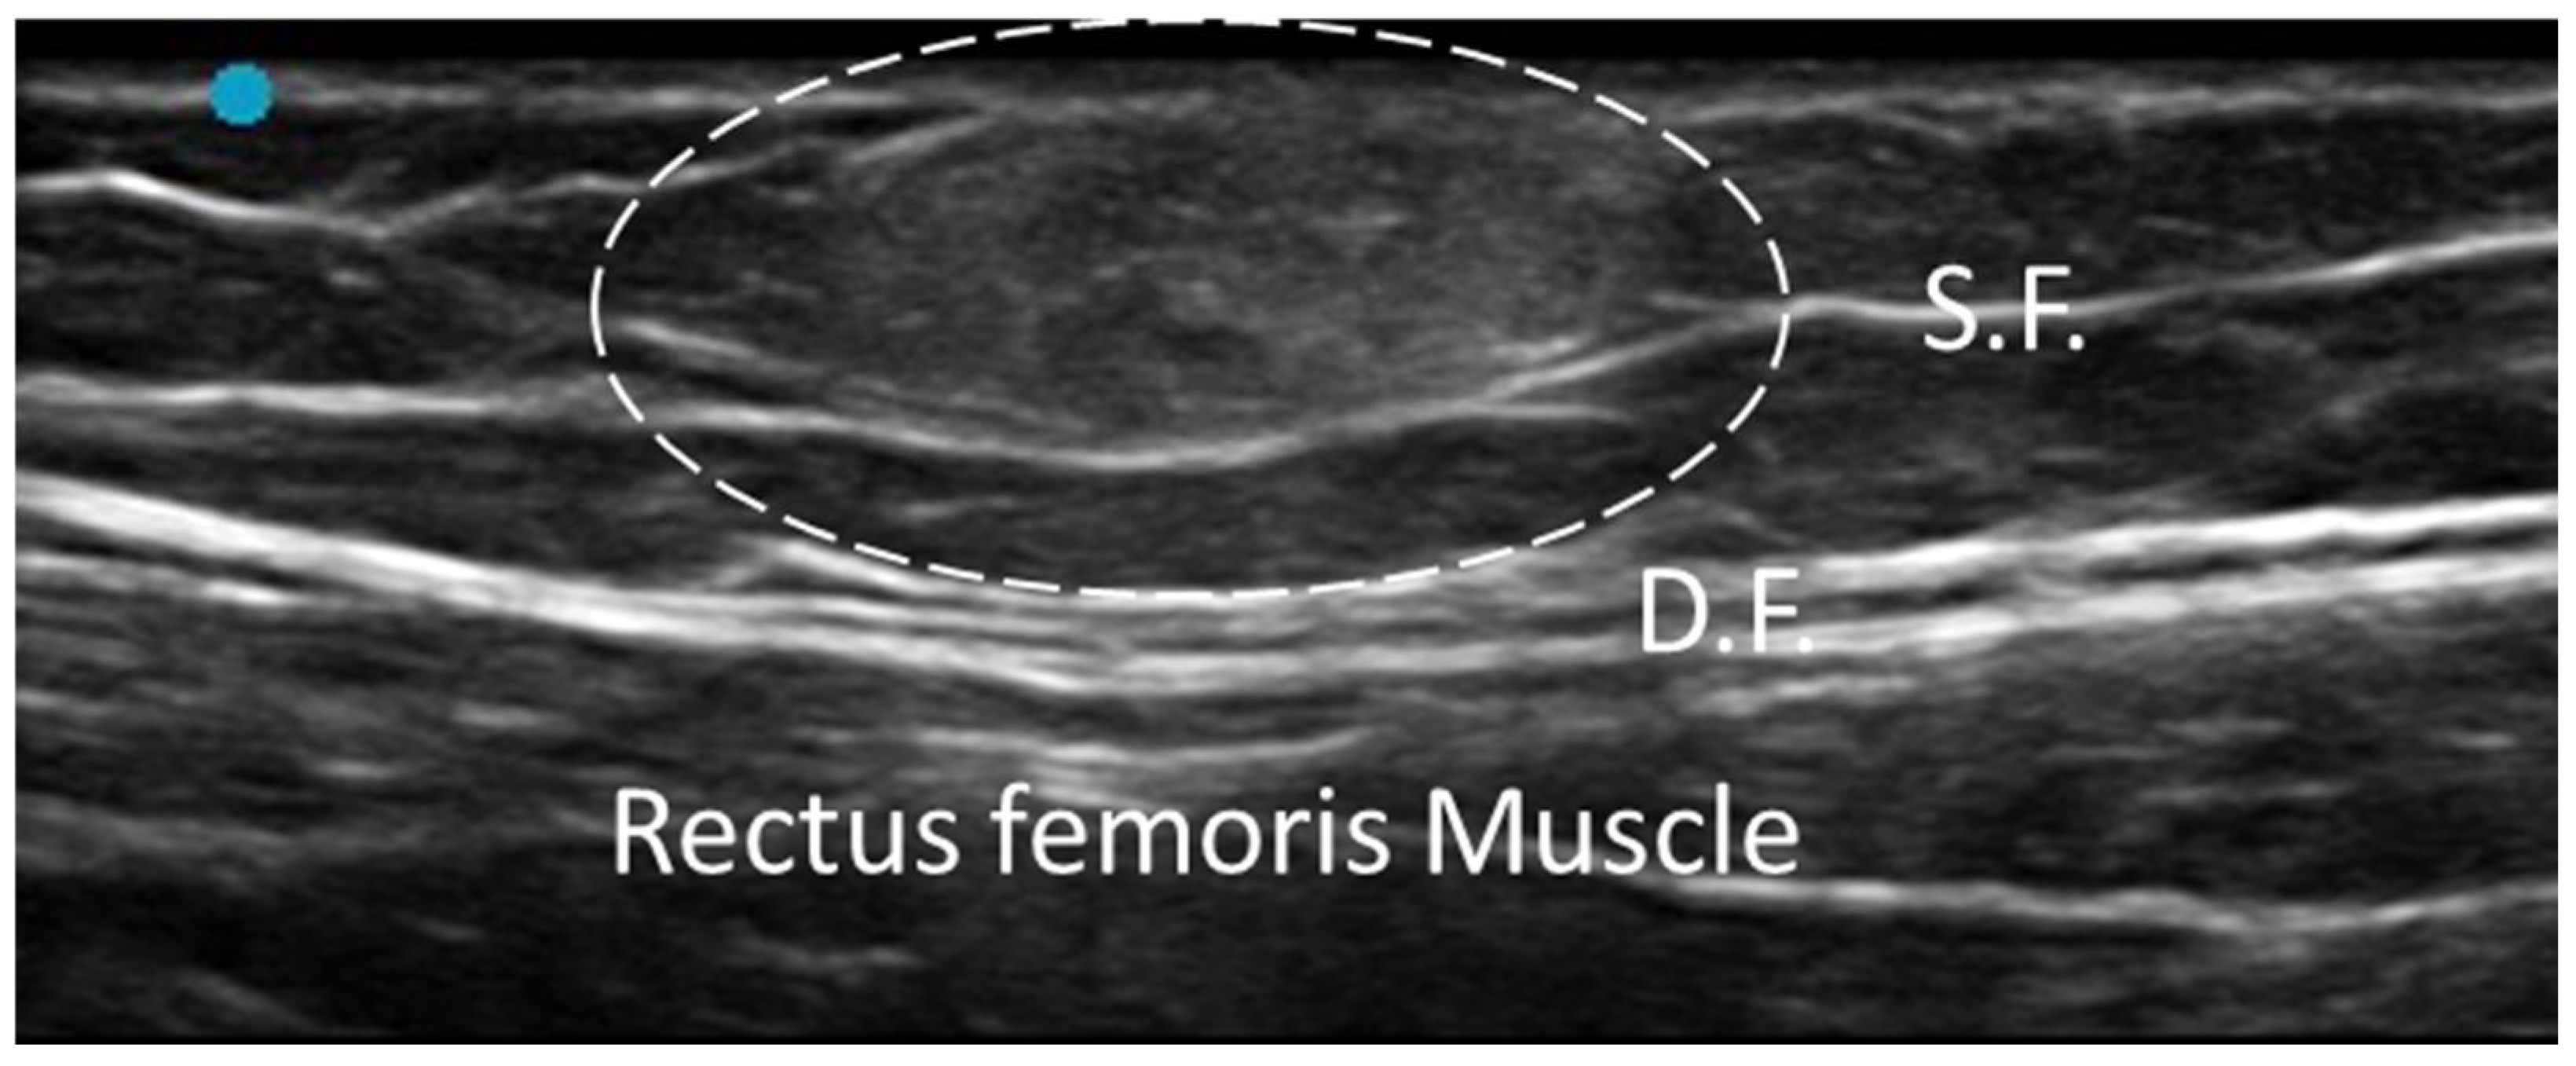

3.1. Normal Ultrasonographic Appearance of Fasciae

- Pirri, C.; Pirri, N.; Porzionato, A.; Boscolo-Berto, R.; De Caro, R.; Stecco, C. Inter- and Intra-Rater Reliability of Ultrasound Measurements of Superficial and Deep Fasciae Thickness in Upper Limb. Diagnostics 2022, 12, 2195. [Google Scholar] [CrossRef] [PubMed] [PubMed Central]

- Warneke, K.; Rabitsch, T.; Dobert, P.; Wilke, J. The effects of static and dynamic stretching on deep fascia stiffness: A randomized, controlled cross-over study. Eur. J. Appl. Physiol. 2024, 124, 2809–2818. [Google Scholar] [CrossRef] [PubMed] [PubMed Central]

- Wilke, J.; Schwiete, C.; Behringer, M. Effects of Maximal Eccentric Exercise on Deep Fascia Stiffness of the Knee Flexors: A Pilot Study using Shear-Wave Elastography. J. Sports Sci. Med. 2022, 21, 419–425. [Google Scholar] [CrossRef] [PubMed] [PubMed Central]